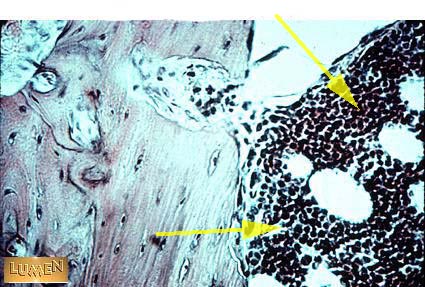

Red Marrow